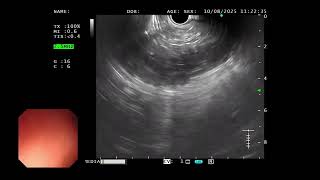

EUS for duodenal duplication cyst